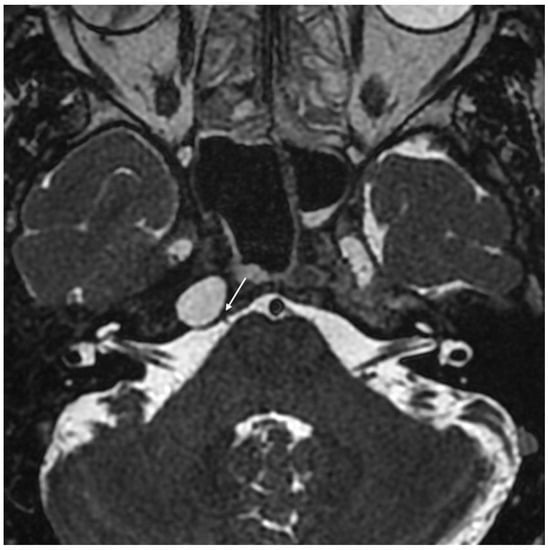

Imaging data from each patient were examined by an expert radiologist and an ENT specialist focusing attention not only on the location of the cyst, but also on the adjacent structures involved. Considering the available literature on symptoms and hypothesized regions of radiological involvement, we established a reproduceable pre-operative radiologic map to better correlate typical symptoms, such as headache, hearing loss, vestibular symptoms, tinnitus, otitis media, diplopia, and facial paresthesia, with PACG. The following regions were considered: (1) temporal lobe/posterior fossa compression (Figure 1); (2) Meckel’s cave compression (Figure 1); (3) Eustachian tube compression/erosion (Figure 2); (4) internal auditory canal erosion (Figure 3); (5) cochlear basal turn erosion (Figure 4); (6) Dorello canal involvement (Figure 5); (7) jugular tubercle erosion. The latter parameter was introduced to evaluate its possible correlation with an atypical clinical presentation, namely fainting. To standardize all these radiological examinations, the jugular tubercle was defined in axial sections as the bony convexity medial to the jugular foramen just above the hypoglossal canal; in coronal sections, it is the bony part directly above the hypoglossal canal (Figure 6).

Figure 1. Coronal T2-weighted MRI demonstrating compression of the temporal lobe and Meckel’s cave region (white arrow) by cholesterol granuloma of the petrous apex.